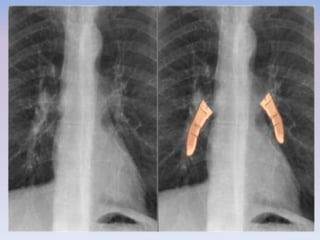

• Used to describe the location of a lesion at the inlet of the thoracic cavity.

• In this anatomical space, the posterior portions of the lung apices are located more

superiorly than the anterior portions .

• A lesion clearly visible above the clavicles on the frontal view must lie posteriorly and be

entirely within the thorax.

• If the cranial border of the lesion is obscured at or below the level of the clavicles, it is

located at the anterior mediastinum

CERVICOTHORACIC SIGN